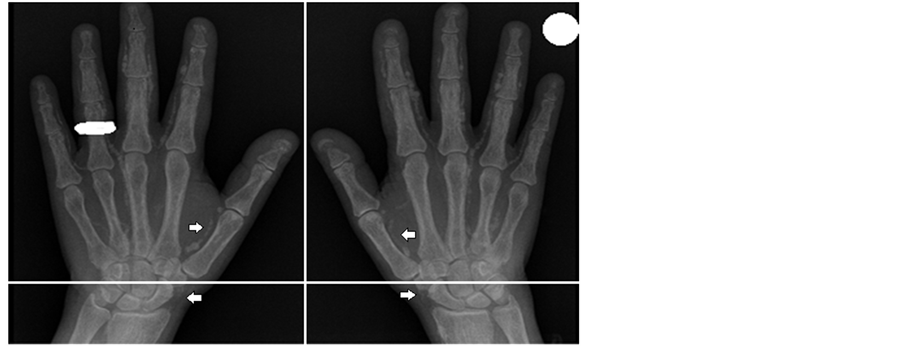

4.6. Distribution of Vascular Calcification

The radiographic films in our study showed that there were 80% calcifications of iliac arteries, 15% calcifications of femoral arteries and 5% vascular calcification in radiograph of the hands. Examples of vascular calcification of the studied patients were presented in Figure 1 and Figure 2.

Figure 1. Bilateral anteroposterior (AP) radiographic views of the hands of a 50-year-old women receiving hemodialysis. Note the calcification of the radial and digital arteries (arrows). Simple vascular calcification score of the hands example is 4.